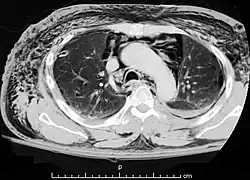

Pneumomediastino

Pneumomediastino (do grego pneuma ar) ou enfisema mediastinal é uma presença anormal de ar entre os pulmões (no mediastino). Descrito pela primeira vez em 1819 por René Laennec.[1] A condição pode resultar de trauma físico ou outra lesão que cause que ruptura das vias respiratórias (como tráquea, laringe ou pulmões) ou da via digestiva (como esôfago e estômago) para a cavidade torácica.